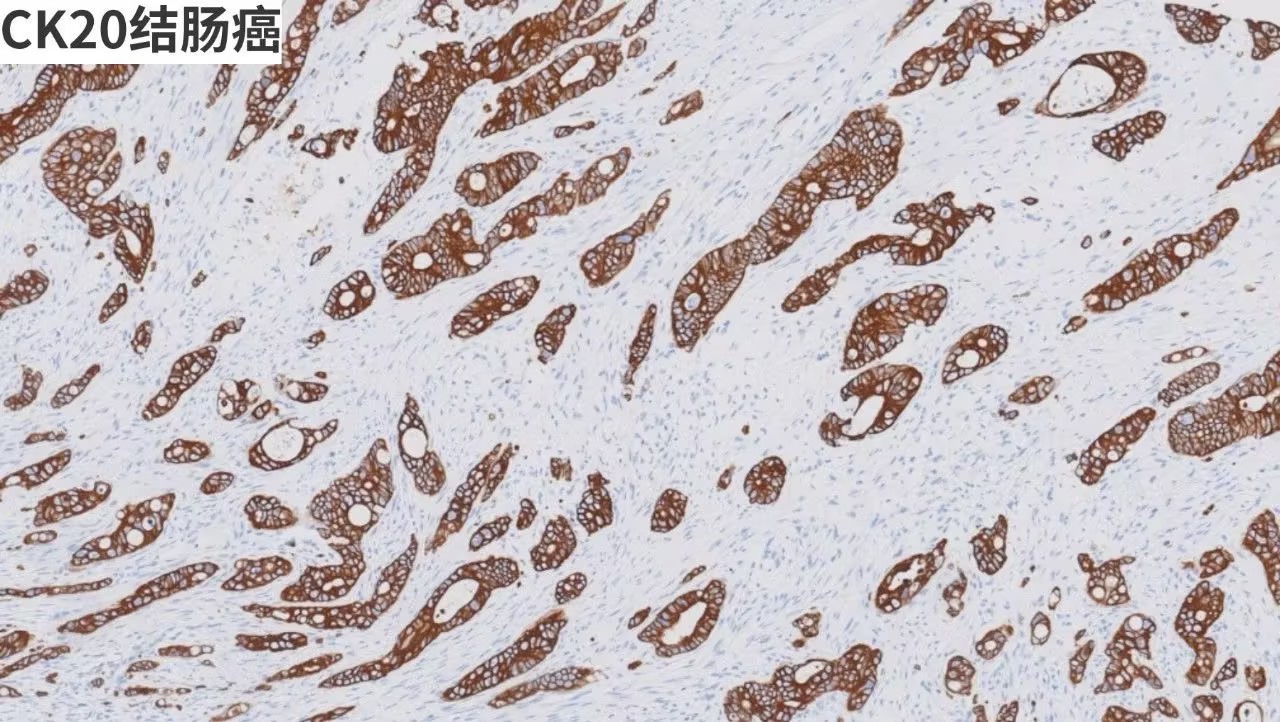

產(chǎn)品染色圖賞析